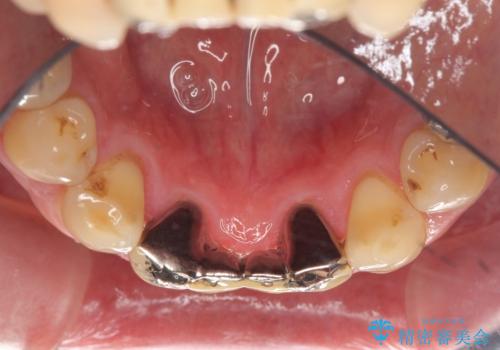

下の前歯のブリッジ 保険治療のやり替え

- 前歯のブリッジのやり替えをご希望されました。

かみ合わせが強く、以前入っていた保険治療のブリッジも前装が欠けてしまっていました。